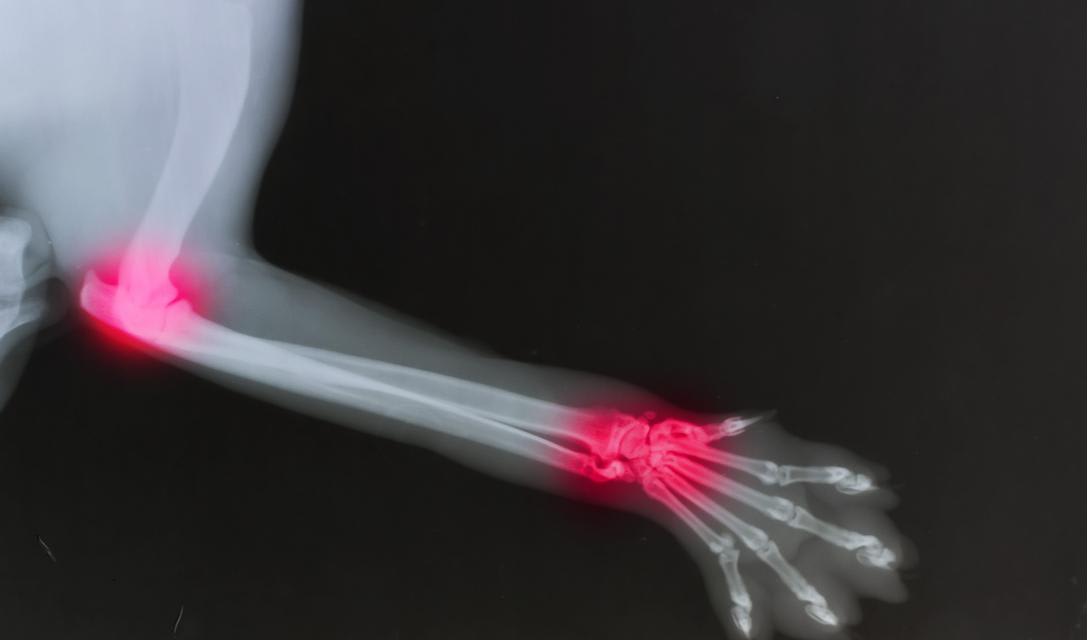

Rheumatoid Arthritis in Dogs: Symptoms, Diagnosis & Treatment

Rheumatoid Arthritis, Immune-Mediated Polyarthritis

The history and physical exam often lead a veterinarian to suspect rheumatoid arthritis. Radiographs (x-rays) are taken and typically show the loss of bone - the bone often appears like holes have been punched in it. The joint surfaces are often irregular and bony spurs coming off of the bone are often seen. A special blood test can be done to look for the rheumatoid factor. Unfortunately, rheumatoid factor is sometimes present in dogs without rheumatoid arthritis, and not all dogs with rheumatoid arthritis test positive for the factor. The synovial fluid may be analyzed and shows characteristic changes. Cells involved in inflammation are present in large numbers, the fluid is usually cloudy and of a thinner consistency than normal. Biopsies of the tissues within the joint can be made and show characteristic changes.